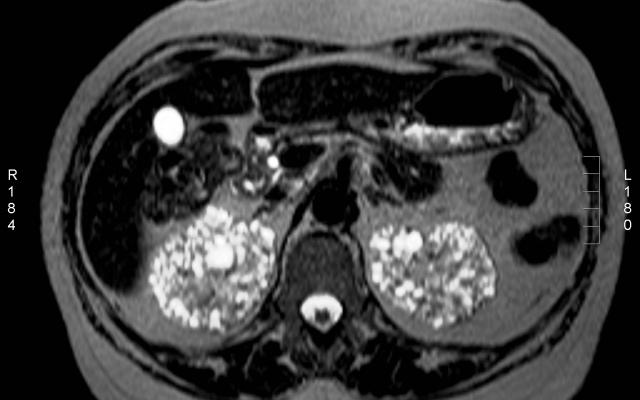

Dit artikel is alleen beschikbaar als PDF.Lees de PDF Artikelinformatie Online verschenen op 4 februari 1963 Citeer dit artikel als Ned Tijdschr Geneeskd. 1963;107:489-94 Heb je nog vragen na het lezen van dit artikel? Check onze AI-tool en verbaas je over de antwoorden. ASK NTVG Ook interessant Diagnose in beeld Een vrouw met een toenemende nierfunctiestoornis Beeldquiz Een vrouw met een toenemende nierfunctiestoornis Stand van zaken Acute nierfunctiestoornissen door niet-steroïde anti-inflammatoire farmaca Meer gerelateerd … Reacties Login om een reactie te plaatsen